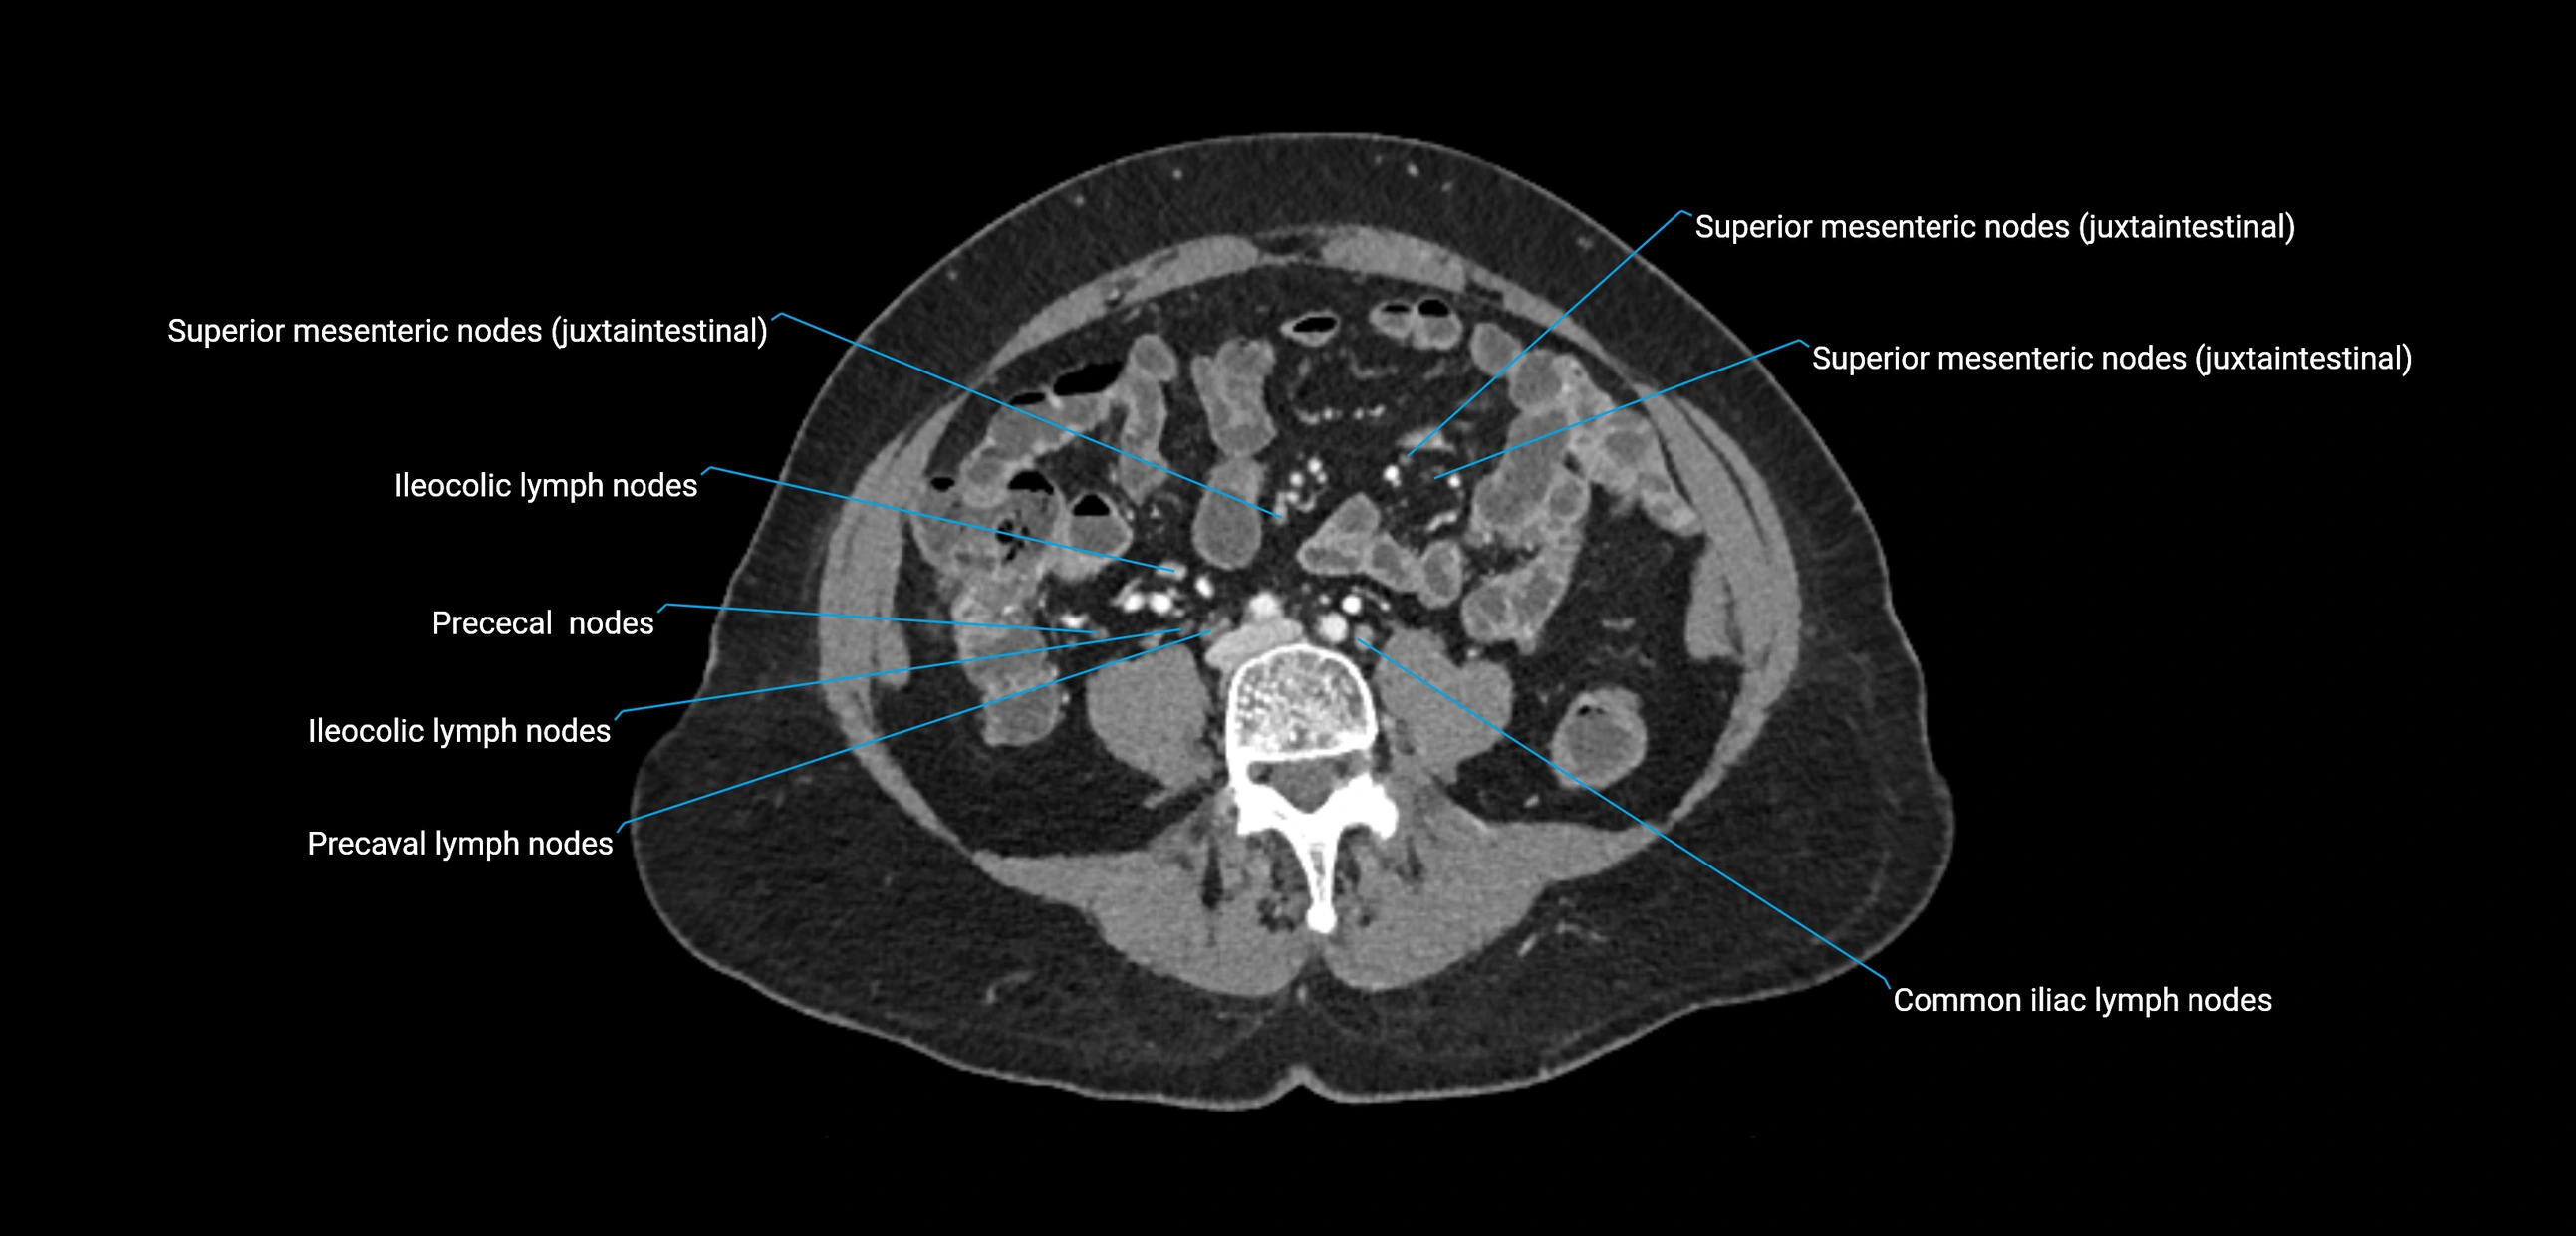

CT image

image